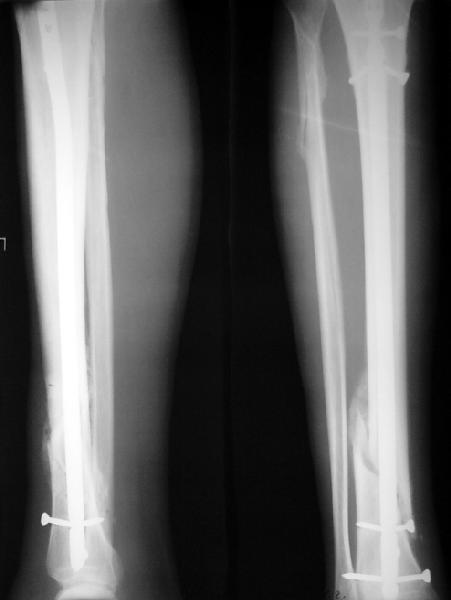

Как мне показать пример? Фото стоящего на одной оперированной конечности пациента? O! Пример, подвигнувший нас на некоторое изменение технологий. Пациент этот ходил с полной нагрузкой вопреки рекомендациям. В качестве подтверждения - сломанный проксимальный статический винт к 1 мес., а к 2 мес. - все остальные. Сейчас мы перешли на более fool-proof остесинтез.